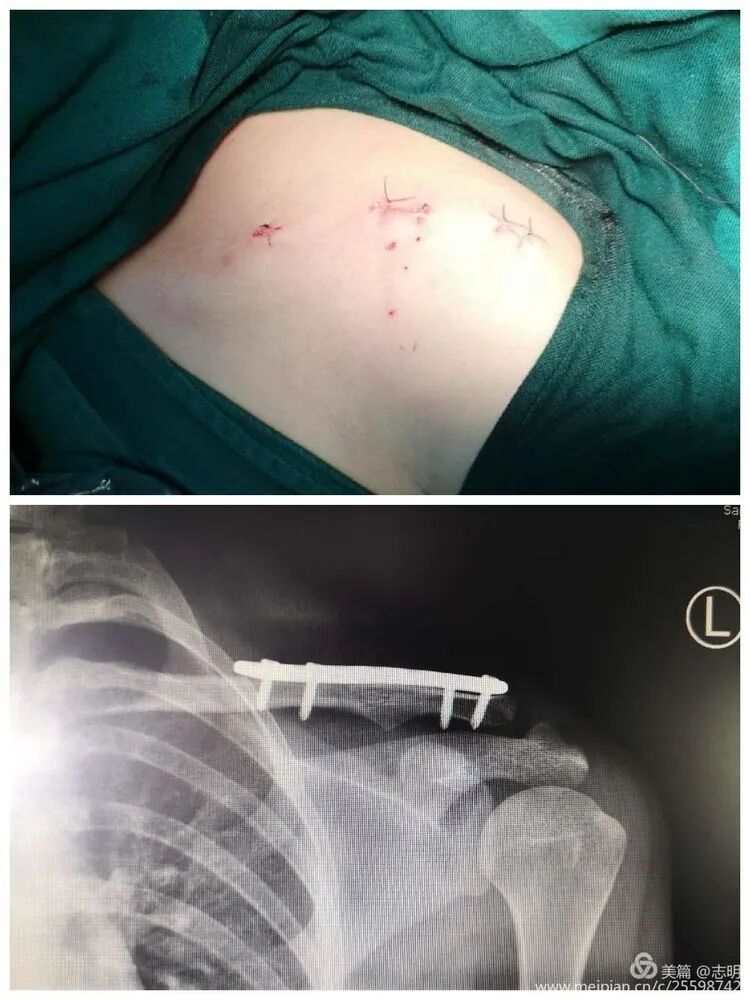

5. Wound Closure

- Close the small skin incisions in layers. Ensure meticulous hemostasis.

-

The cosmetic outcome is significantly enhanced by these minimal incisions.

- Close the small skin incisions in a layered fashion. Ensure meticulous hemostasis to prevent hematoma formation, which can compromise the cosmetic outcome and increase infection risk.

The primary cosmetic advantage of MIPO derives from these minimal incisions, resulting in significantly less visible scarring.

(Clinical image of small, well-healed MIPO incisions). -

(Another clinical view of minimal scarring). -

(Close-up of a small post-operative incision). -

(Clinical view of small post-operative incisions). -